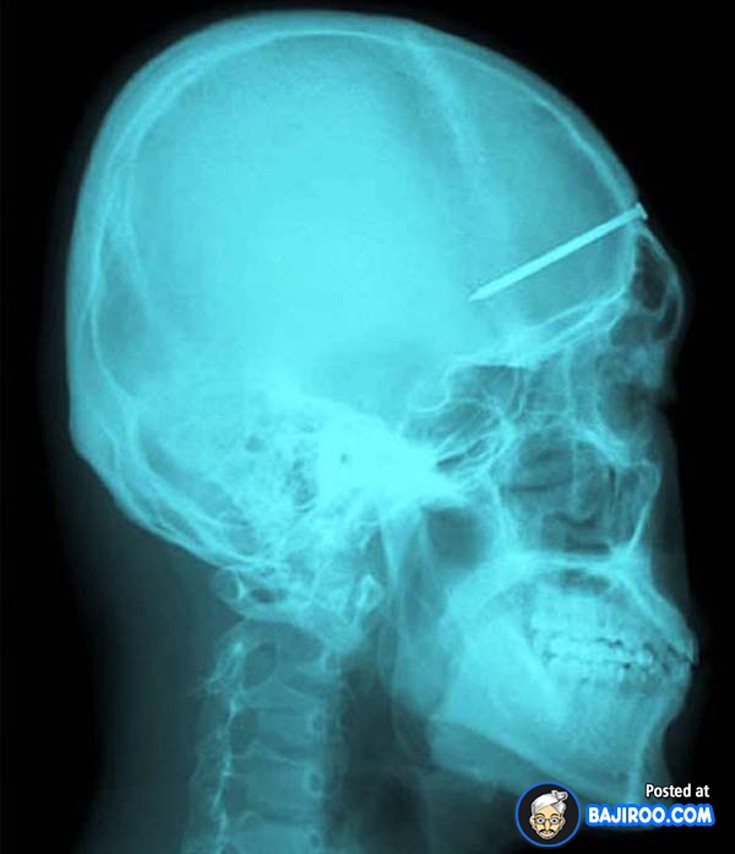

Ο,ΤΙ ΝΑ 'ΝΑΙ #ακτινογραφίες Παράξενα πράγματα που έχουν δείξει οι ακτινογραφίες Από δαχτυλίδια μέχρι πιρούνια και καρφιά - Δείτε τις φωτογραφίες 15·04·2016 11:08 1 σχόλια